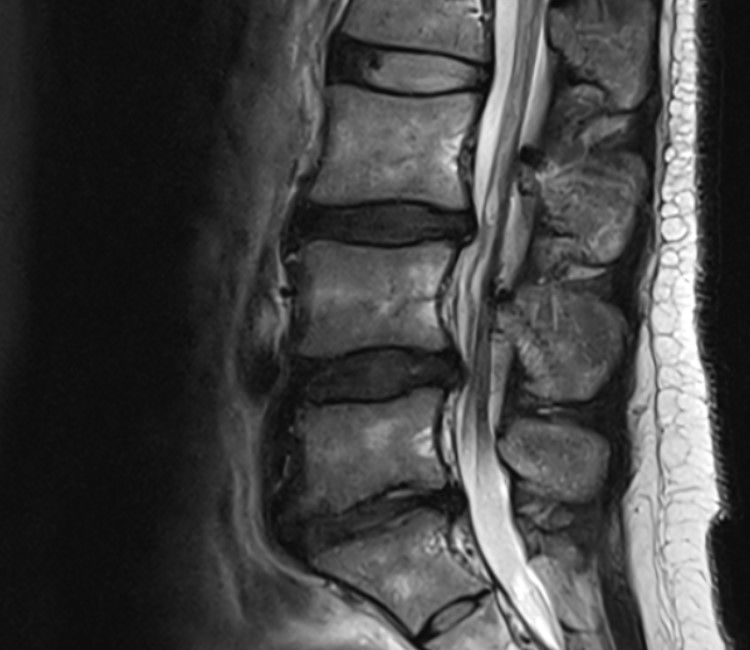

mri 상태가 그렇게 안좋은가요??ㅜㅜ

통증은 크게 없는데 상태가 심하게 안좋다고 하는데

• 2번 째 사진

MRI 상에는 디스크가 일정 부분 돌출되어있어 심해보이긴 합니다. 하지만 저희 몸이라는게 꼭 디스크가 돌출되었다가 모든 사람이 아픈것은 아닙니다. 정말 통증이라는 부분은 뇌에서 느끼고 반응하는 것이기 때문에 사람마다 다를 수 있습니다. 저렇게 되어도 통증이 없으면 일상생활 하셔도 됩니다. 하지만, MRI까지 찍으신거 보면 허리가 뭔가 문제가 있으니까 찍으신거같은데, 현재 영상자료로도 심해보이긴하여서 걷기 정도 하시는게 좋을거 같습니다. 그리고 걷기도 만보 보다는 처음에는 2~3천보에서 시작해서 점점 늘리시는게 좋을것으로 보입니다. 부디 잘 회복되시길 바라겠습니다. 감사합니다.

허리 디스크가 돌출 혹은 파열이 발생하여 주변의 신경을 압박하거나 염증이 발생하는 상태로 보여지는데요, 가벼운 산책과 같은 운동은 크게 건강에 악영향을 주지는 않습니다. 그러나, 갑작스럽게 만보정도 걷게 되는 경우에는 운동량 증가에 의해서 불편감이나 통증이 발생할 수 있기 때문에, 적절한 운동량부터 시작해보시는 것이 좋겠습니다. 또한, 코어근력을 증가시켜 척추의 안정화를 위해 데드버그나 버드독과 같은 기초적인 코어운동을 해보시는 방법도 고려해보시는 것을 추천드리겠습니다.

디스크가 심한 편이기는 하네요

요추 디스크가 밀려나와 신경을 자극하는 양상으로 저림증이나 통증이 생길 수 있겠습니다.